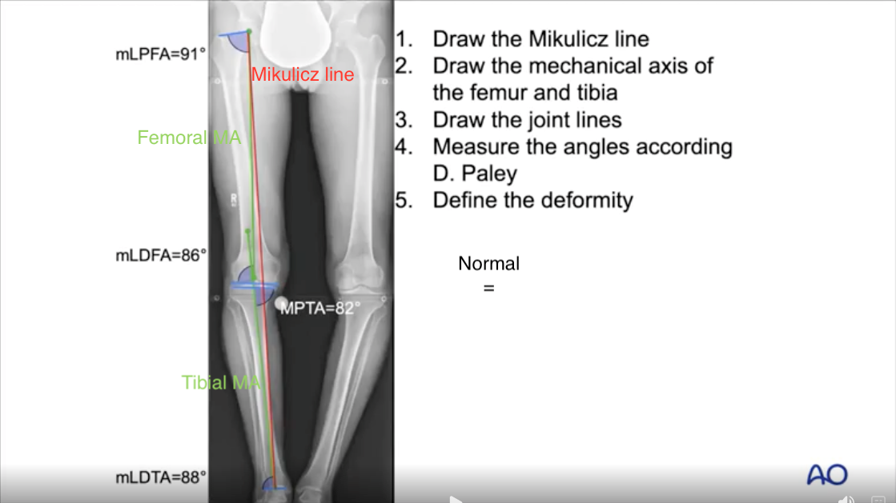

Analyzing the deformity in the frontal plane allows a check of where the limb’s mechanical axis (MA) crosses through the knee joint. Also called the Mikulicz line, this axis extends from the center of the hip to the center of the ankle. If it does not also pass through the appropriate part of the knee joint, i.e., slightly valgus, the knee is malaligned.

The MA deviation is the distance between the Mikulicz line’s intersection point and an appropriate joint line intersection point. The intersection point is normally expressed as a percentage of the Tibia width from medial to lateral, with the medial edge being 0% and the lateral edge being 100%. Very severe varus values can be negative percentages; extreme valgus values can be greater than 100%. The optimal MA intersection point is 65–70%.

Using a frontal plane view, the relevant angles are measured following Dror Paley’s technique. Rather than using the Mikulicz line, Paley used two separate lines, one running down from the middle of the hip to the target MA/joint-line intersection, and one running up from the middle of the ankle through the same point. With these in place, the angles of the hip, the knee (femur and tibia) and the ankle can all be determined, as well as the mechanical tibiofemoral angle (mTFA) (normally 0-2 degrees). And finally there’s the joint line convergance angle (JLCA), i.e., the angle across the joint between the distal femoral and proximal tibial surfaces. Like the mTFA, the JLCA is normally 0– 2 degrees. A knee with a JLCA greater than 2 degrees is varus; one with a negative JLCA is valgus.

In every possible case, a frontal weight-bearing long leg radiograph should be taken, along with any other appropriate views, e.g., a Goldberg view. As noted above, the leg rotation should center the patella between the two condyles. Using the available software, you can measure all of the necessary parameters for a thorough deformity analysis. By comparing your measurements with normal values, you can plan for the best possible treatment.

Based on that standard long x-ray, planning an osteotomy has five main steps:

- Define the malalignment

- Locate the deformity

- Define the target alignment axis

- Decide which osteotomy is required and location of hinge point

- Measure the correction angle with the Miniaci method

1. Defining the malalignment

To define the malalignment, a Mikulicz line must be drawn, i.e., from the center of the femoral head to the center of the ankle. If that line crosses the knee joint medially of the normal range, the alignment is varus. If the deviation is greater than 15mm, it is considered obvious varus. If it crosses laterally of that range, the alignment is valgus. The threshold for an obvious valgus malalignment is 10mm. The designation of obvious is an important indicator for osteotomy correction.

2. Locating the deformity

As noted earlier, the deformity can be located by drawing the mechanical axes and joint lines, measuring the relevant angles and comparing the results with normal values. Where intraarticular deformity is also present, this will normally self-correct when the bones are realigned. Therefore, we need to remember to subtract the predicted changes in the lateral and medial joint gaps from the overall correction.